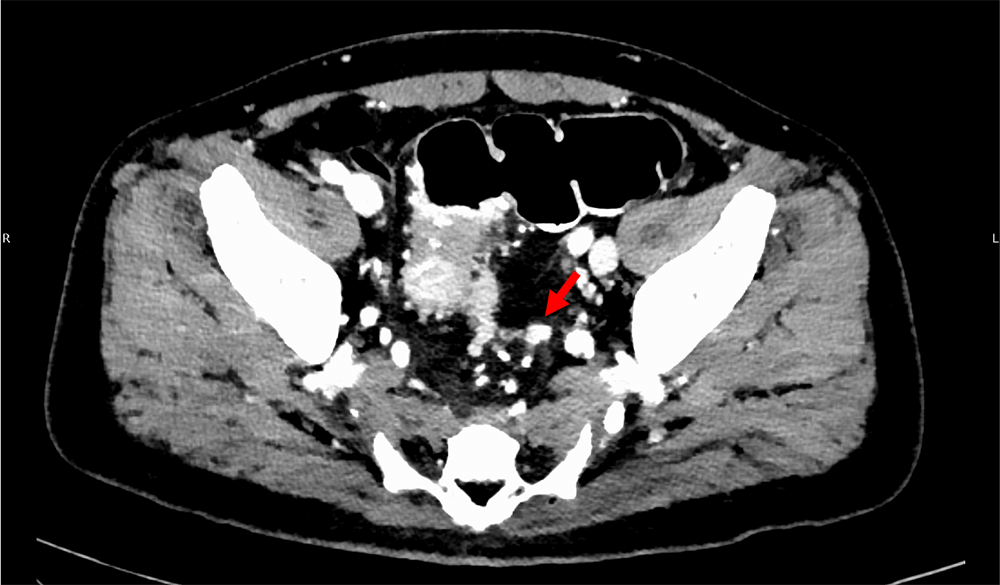

図5.門脈相(120kVp画像)、水平断

直腸左側に不定形の小結節が同定され、TD(矢印)が疑われる。

図6.門脈相(120kVp画像)、水平断

TD(矢印)の背側に静脈の走行が明瞭に確認できる。

また直腸癌の予後不良因子である壁外静脈浸潤(EMVI)、tumor deposit(TD) の同定は重要であることが知られている。これらはMRIで診断されることが一般的であるが、造影CT検査でも指摘できることがある。仮想単色X線エネルギー画像(MonoE)は低エネルギー帯でヨードの造影効果が劇的に増加するため、病変や脈管の視認性が向上するので、検出能や診断確信度の向上に寄与すると考えられる。